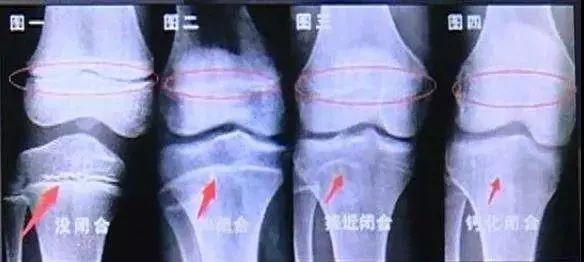

骨龄评估的准确性和成年身高预测非常相关。目前医院常用的骨龄评估的方法主要是G-P骨龄图谱法和软件辅助评定骨龄。简单的说骨龄图谱法是根据各年龄段骨成熟的标志,以及对比干骨后端融合过程来判断骨龄(大部分医院采用)。